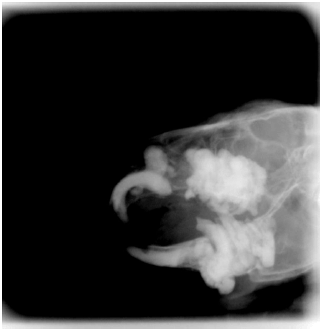

不整咬合

歯の噛み合わせの異常です。

ウサギは完全な草食動物で、前歯も奥歯も生涯伸び続けます。

普通は草を噛むことによって歯が擦れて短くなるので伸び過ぎにはなりませんが、十分に草を食べていないと歯が短くならず、噛み合わせが悪くなってしまいます。

伸びた歯が口の中を傷つけるため、痛みで食欲が落ちたり、歯の根元で炎症が起こったり膿が出たりします。

治療は伸び過ぎた歯を切ったり削ったりしますが、一度噛み合わせが崩れた歯は完全に元には戻りません。

普段から干し草をしっかり与え予防することが何よりも大切です。